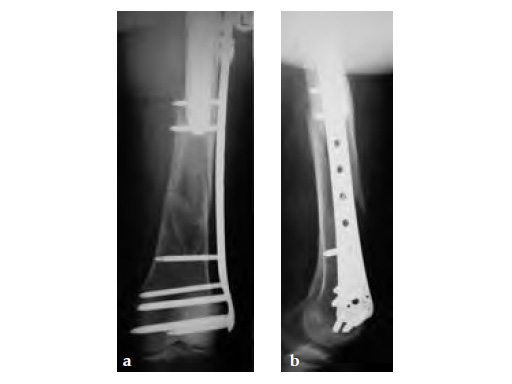

Case 1: A 78-year-old female sustained a periprosthetic fracture, Vancouver type C, 9 years after a total hip arthroplasty.